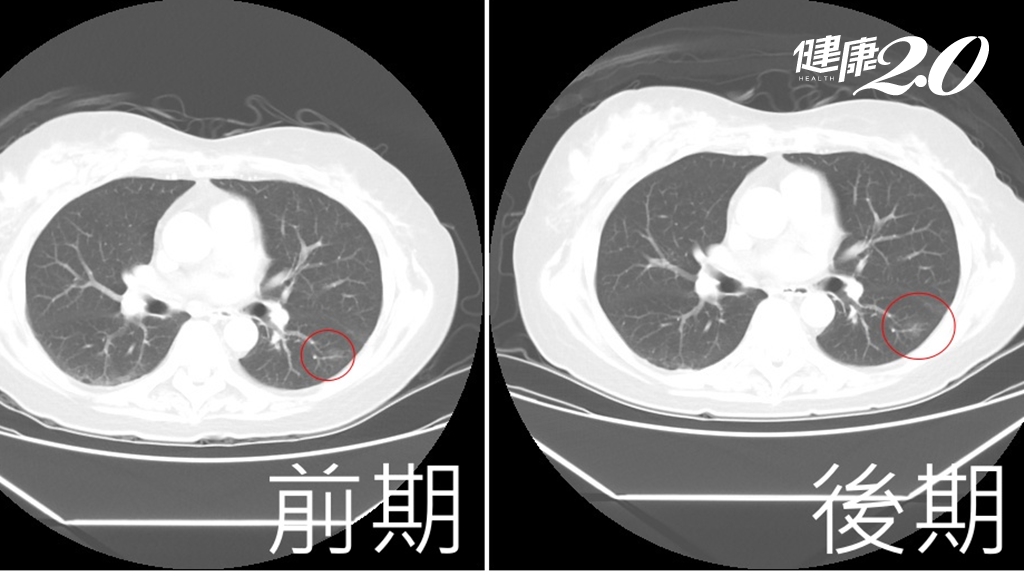

◎ 圖片來源/翻攝自林美照臉書